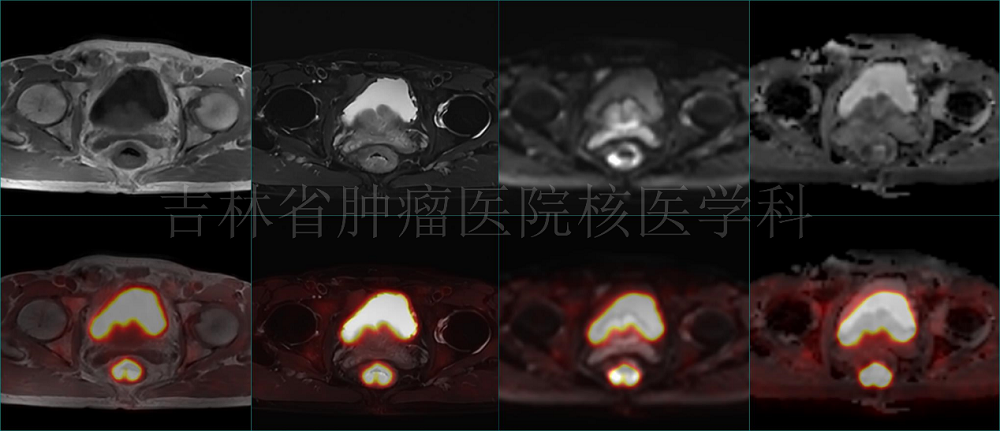

病例2 PET/MR直腸癌治療前分期:直腸癌T2N0M0